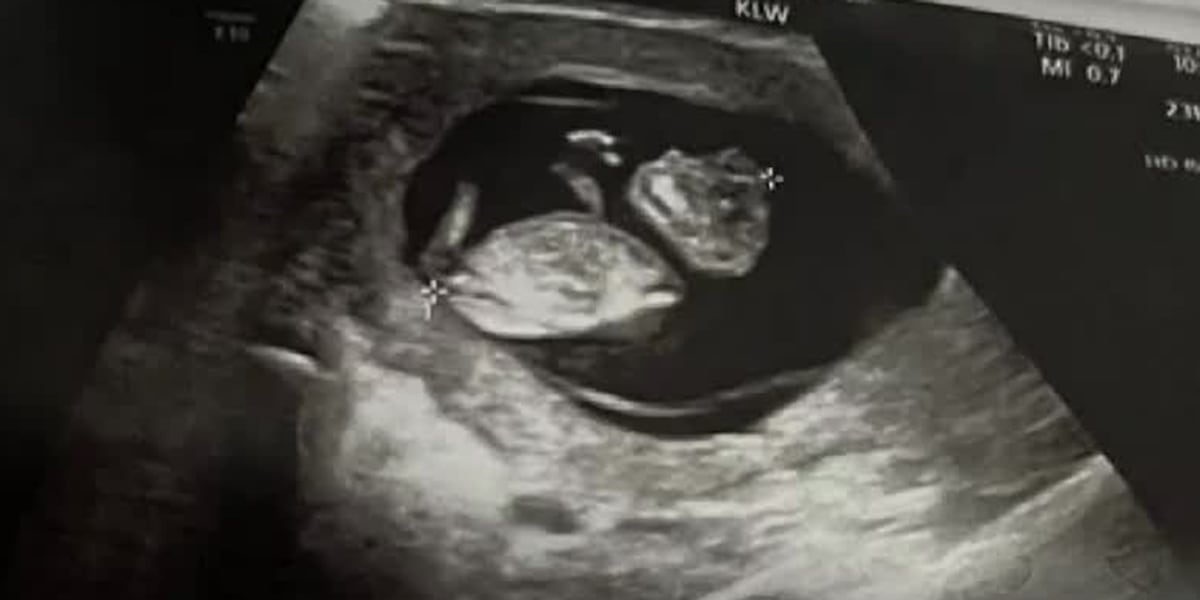

This is the result of lawmakers getting in between doctors and women. Nancy Davis of Baton Rouge is carrying a fetus with a rare condition where the baby's skull fails to form. It is fatal. Since her life is not in danger and the condition is not on the list of qualified conditions allowing abortion, Ms. Davis will either have to carry the fetus to term to have it die within an hour or travel to another State.

Mother claims she was denied an abortion despite baby’s condition

A Baton Rouge mother has a week to make an unthinkable decision - carry her baby to term even though she says doctors tell her it will not survive or find another state where she can have an abortion.